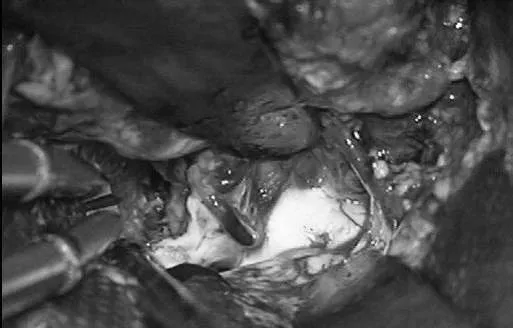

Lawton教授术中操作

▼左侧翼点开颅,再次手术,显露前颞叶

▼沿颞下回经原皮层入路达颞角

▼AChA经脉络裂进入颞角,在前方供应AVM,lPChA在后方供应AVM

▼通过ITG经皮层显露可以充分显露颞角,达到全切AVM